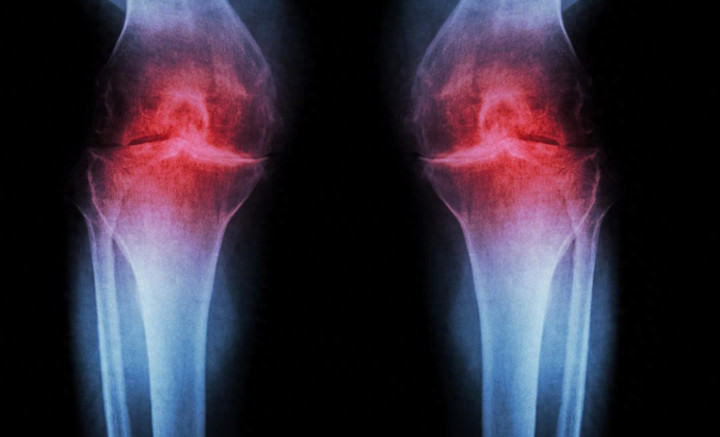

对小鼠膝关键切片进行红色染色后发现,即即是在乐龄小鼠中,调整后软骨层也彰着增厚。

在膝骨关键炎这一慢性关键疾病中,软骨逐步磨损,软骨细胞会开释炎症信号,关键失去原有的顺滑贯通智力。

清寒新的软骨层后,骨与骨之间摩擦加重,出现肿胀,日常算作如馈送或障碍楼梯齐会变得繁重。